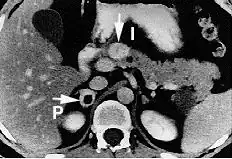

Tomografia komputerowa (TK) jest badaniem ogólnie dostępnym, charakteryzującym się dużą czułością (95–98%[16]). Guzy chromochłonne w obrazie TK charakteryzują się zwykle jednorodną strukturą i owalnym kształtem. Niekiedy można uwidocznić zmiany torbielowate, ogniska martwicy, wylewy, zwapnienia w świetle guza. Przy złośliwych postaciach pheochromocytoma istotna jest również możliwość zlokalizowania potencjalnych przerzutów.

Przy trudnościach diagnostycznych, zwłaszcza w przypadku guzów zlokalizowanych pozanadnerczowo, stosuje się rezonans magnetyczny. Uważa się, że właśnie w przypadku takiej lokalizacji rezonans wykazuje większą czułość. Przydatny jest również w różnicowaniu innych zmian w nadnerczach. Minusem metody jest mniejsza dostępność i swoistość oraz wyższy koszt.